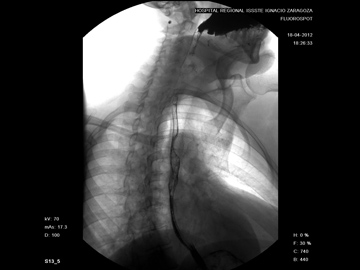

SerieEsofagogastroduodenal